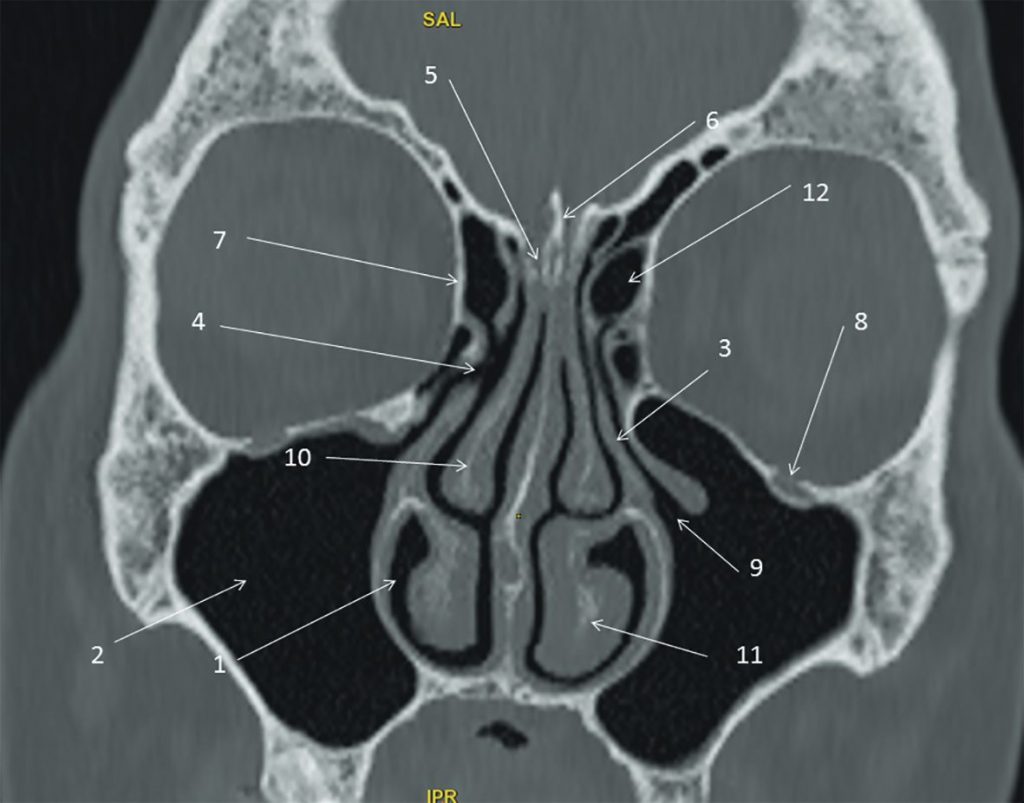

Fig. 62.4 Sinus : scanner, coupe frontale.

1. Fosse nasale. 2. Sinus maxillaire. 3. Processus unciforme. 4. Méat moyen. 5. Lame criblée. 6. Crista galli. 7. Lame orbitaire de l’ethmoïde. 8. Foramen infraorbitaire (V2). 9. Infundibulum du sinus maxillaire. 10. Cornet moyen. 11. Cornet inférieur. 12. Cellules ethmoïdales.

Source : CERF, CNEBMN, 2022.